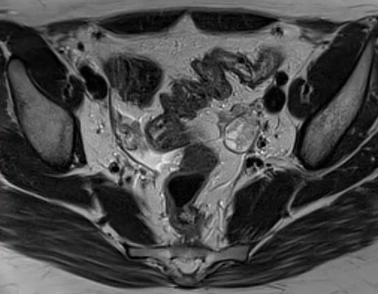

Pelvis : Caractérisation des masses annexielles de l'abdomen aigu à l'incidentalome